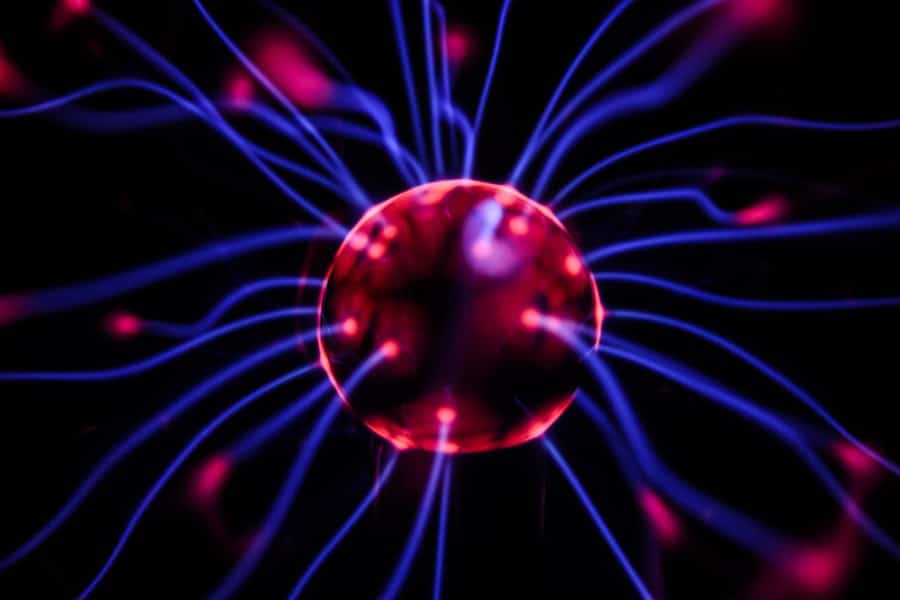

Your brain plays a pivotal role in how you perceive and process pain. When you experience an injury or any form of discomfort, sensory neurons send signals to your spinal cord, which then relays this information to your brain. The brain interprets these signals, allowing you to recognize the sensation as pain.

However, in the case of neuropathic pain, this process can become distorted. The brain may misinterpret normal signals or generate pain sensations without any external stimuli. This miscommunication can lead to heightened sensitivity, where even light touch can provoke intense pain.

This phenomenon is known as allodynia. Additionally, your brain’s emotional centers can influence how you experience pain. Stress, anxiety, and depression can amplify your perception of pain, creating a vicious cycle that can be difficult to break.

Understanding the brain’s role in processing pain is essential for developing effective treatment strategies that address both the physical and emotional aspects of neuropathic pain.